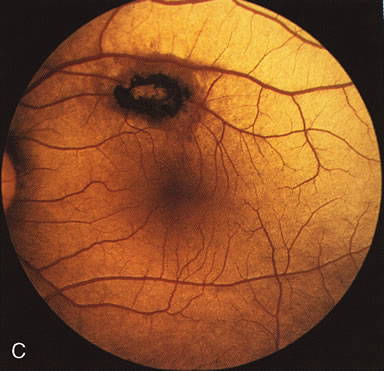

In CACD the bilateral macular lesions are solitary, circumscribed, and circular or ovoid in shape. They are unassociated with other findings such as drusen or flecks. FA will confirm the well-circumscribed area of choriocapillaris atrophy and further document that there are no associated findings that would lead to secondary choroidal atrophy in disorders such as age-related macular degeneration, Stargardt's fundus flavimaculatus, or dominant drusen of Bruch's membrane11 (Fig. 7 A and B).

Fig. 7. Central areolar choroidal dystrophy. The presence of choroidal atrophy in this well-circumscribed macular lesion (A) is confirmed by persistent visualization of the larger choroidal vessels as seen on angiography (B). Peripapillary (pericentral) choroidal dystrophy. The areas of choroidal atrophy are well-demarcated and contrast with the areas of normal choroid (C, D). Crystalline retinopathy (of Bietti). The areas of choroidal atrophy correspond to areas of the retina where crystals are not present (E, F).

Peripapillary (Pericentral) Choroidal Dystrophy

Peripapillary choroidal atrophy radiates from the optic nerve along the temporal vascular arcades. The macula is affected later in the course, and this is usually responsible for the onset of visual symptoms. FA shows the choroidal atrophy and the early macular changes (Fig. 7C and D).